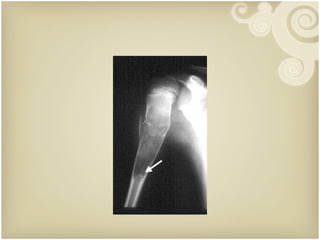

Green Stick Fracture

Torus Greenstick Green Stick Fracture

Torus Greenstick GreenStick Fracture

• #12 Figure 8-178 Greenstick fracture. In the humerus of this elementary school child, a direct blow from the direction of the arrow has caused an incomplete transverse fracture.